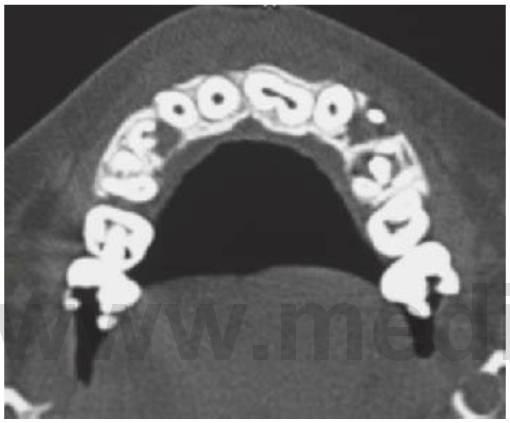

- Resulta esencial localizar la posición del diente que debe extraerse antes de la cirugía. Pueden realizarse radiografías periapicales que emplean la técnica del desplazamiento del tubo (tube-shift) para localizar el diente, pero siempre entrañan la posibilidad de errores e interpretaciones erróneas. De la misma manera, pueden utilizarse radiografías panorámicas y oclusales maxilares estándar. La proyección oclusal de vértice permite obtener una muestra más precisa de la localización horizontal y anteroposterior, por lo que es la preferida (fig. 9.8C) para ayudar a determinar el procedimiento quirúrgico óptimo. Algunos centros prefieren no utilizar esta vía debido a una excesiva radiación en el cráneo.

- Las técnicas digitales de imagen que utilizan tomografías de haz cónico proporcionan una buena definición e imágenes tridimensionales de la cabeza y el cuello y emiten mucha menos radiación que la tomografía computarizada tradicional (TC) (v. fig. 9.18 más adelante).